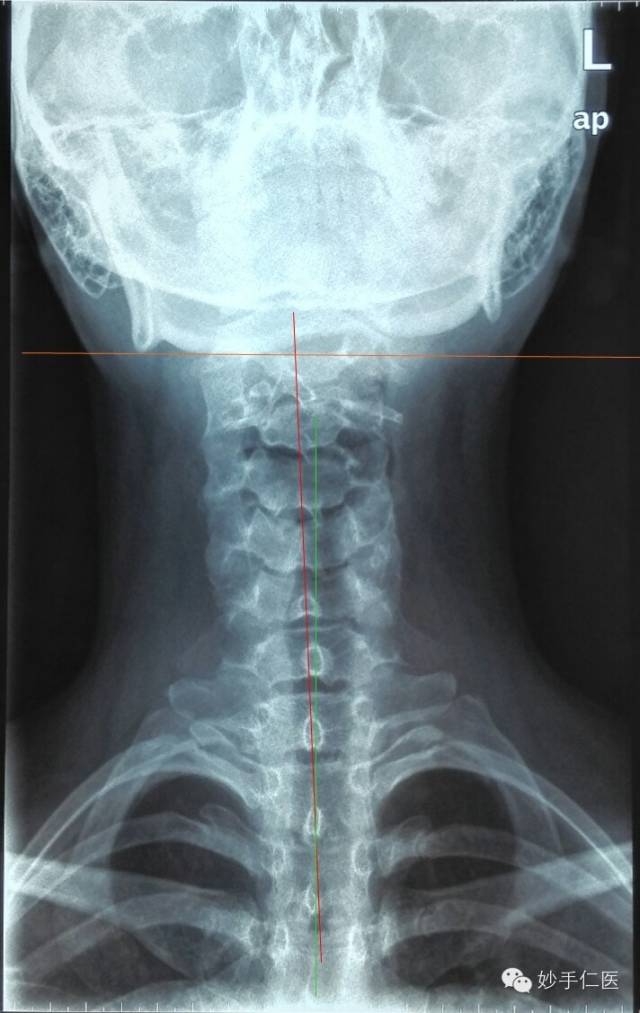

颈部正位片子:头颅向右侧偏歪,颈椎和胸椎存在微小侧弯。